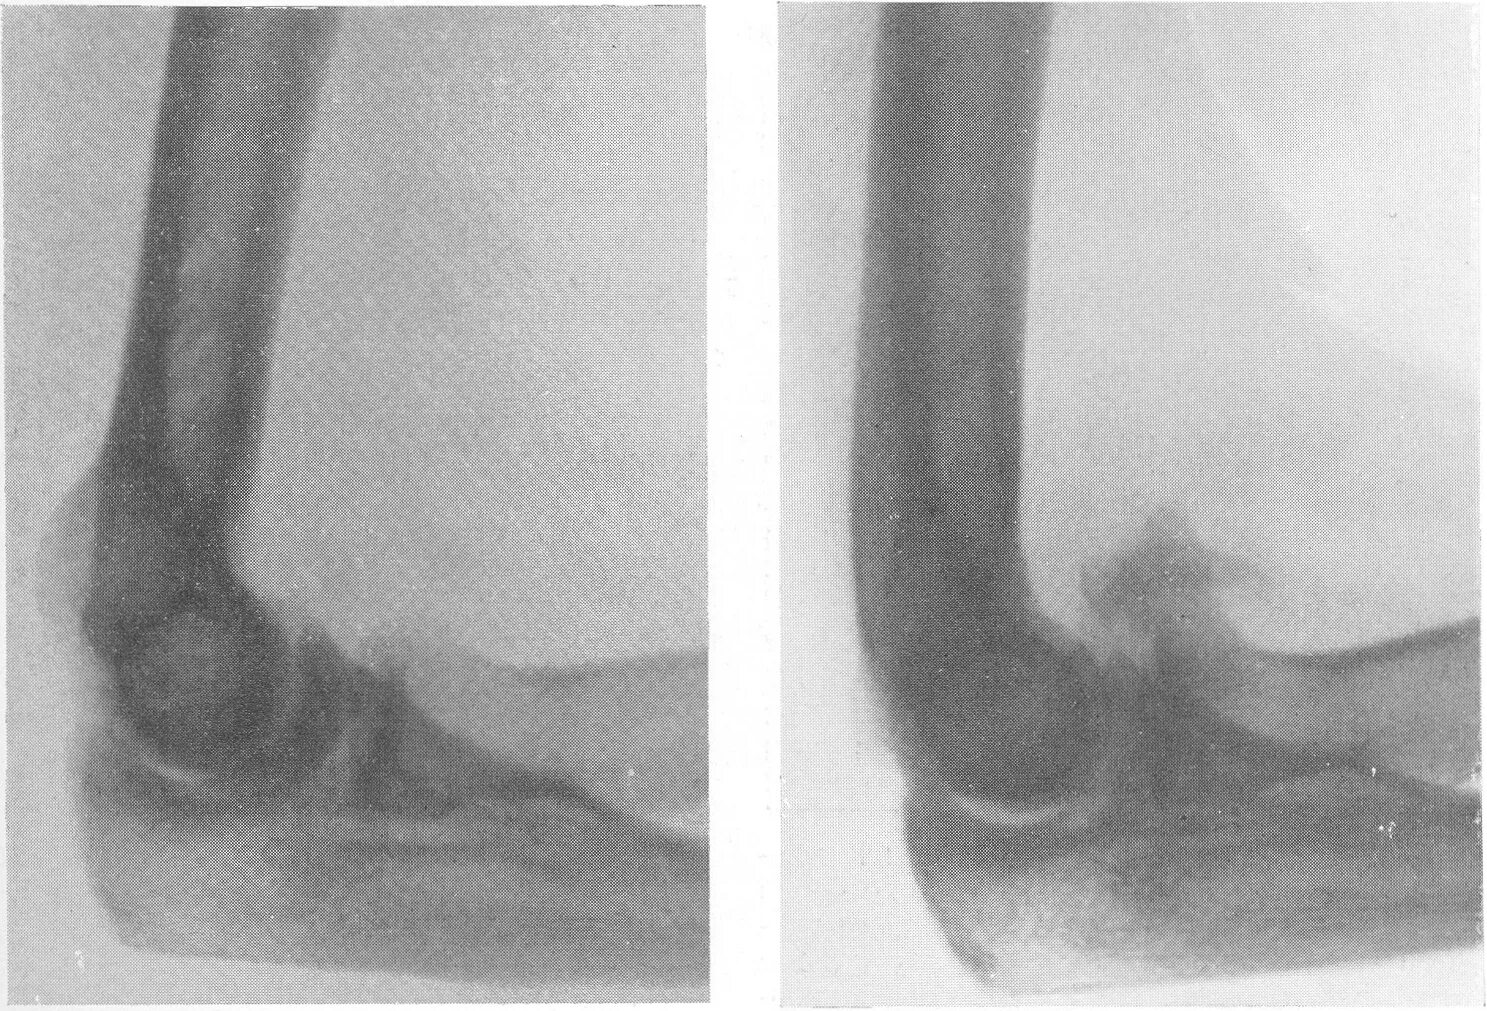

Оссифицированный миозит